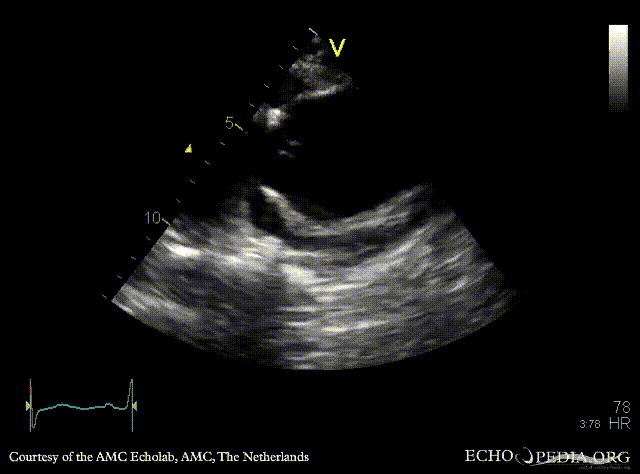

PLAX: Color Doppler, severe aortic regurgitation A4CH: dilated left ventricle